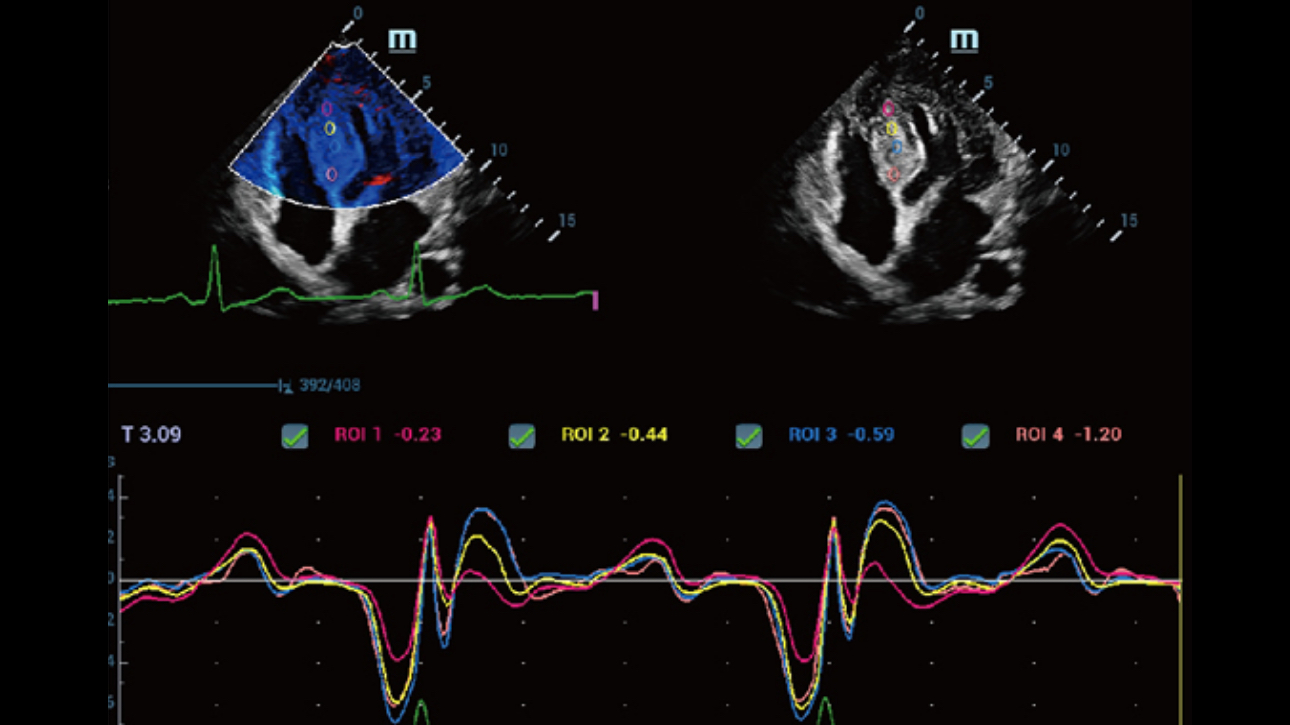

HD Scope: By processing channel data retrospectively, HD Scope enables tissue-specific enhancement with improved detailed information and image contrast on specific region of interest.

As ZST+ captures and stores the complete acoustic raw data set. Total Recall Imaging allows system to do retrospective processing on channel data and also permits users to modify numerous imaging parameters on stored images to maximize clinical output.